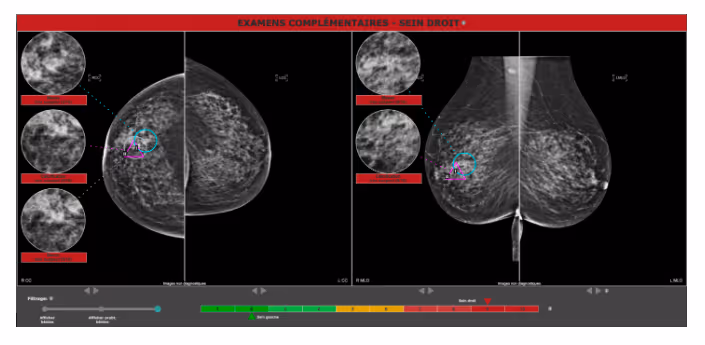

Ferrum Health partners with best-in-class AI providers, offering solutions to reduce radiology workload and improve patient care.Therapixel Case Study: AI Helps to Avoid ErrorsIntroductionAI-guided breast cancer detection system, such as MammoScreen, provides radiologists the reassurance and avoid errors.Clinical case

- A 71-year-old female requests a second opinion

- A palpable right breast mass had been negated 1 month prior

- Utilizing MammoScreen on the second image, the mass was detected with a score of 9

- The mass was found on ultrasound with a measurement of 20mm and an MRI shows a large mass

- With the high score, the AI could have alerted the first radiologist, fortunately, the patient requested a second opinion

- Biopsy result: invasive ductal carcinoma grade 3